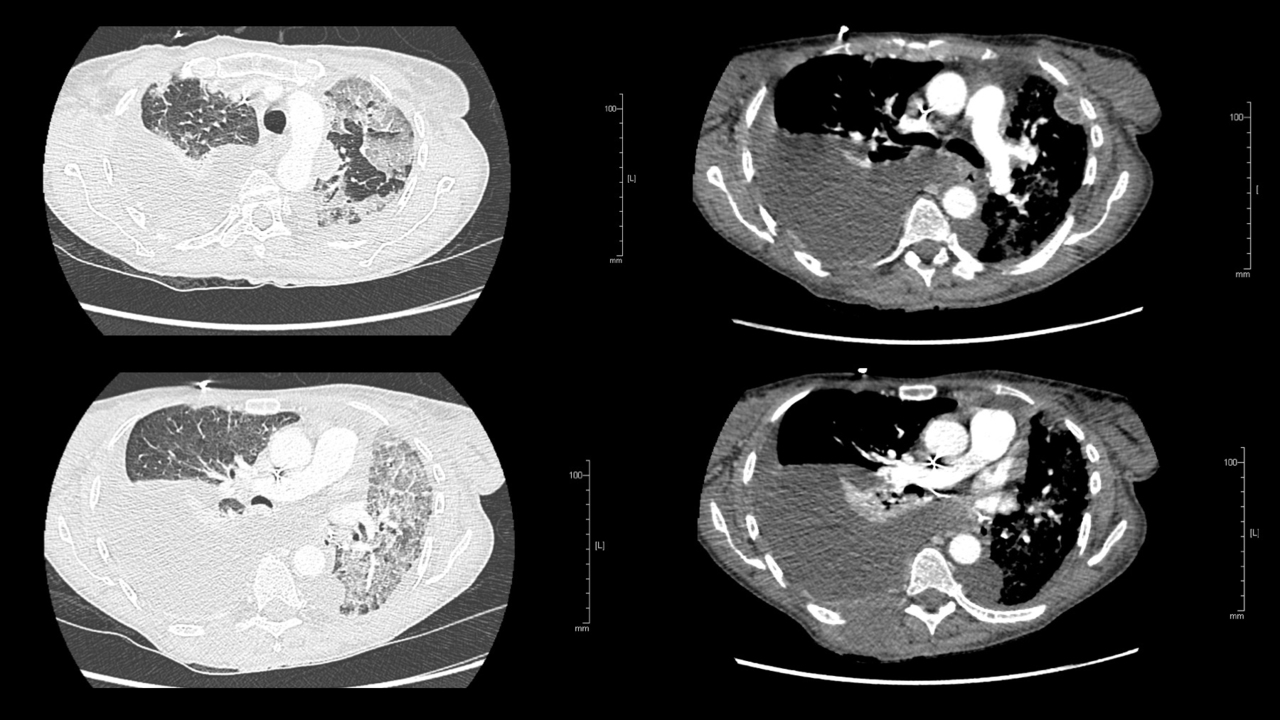

Voici les résultats du scanner que vous avez réalisé en urgence.

Question n°14 : À ce stade de la démarche diagnostique, vous envisagez comme hypothèse(s)

Possible lymphangite carcinomateuse et pleurésie maligne

Absence de defect endoluminal des artères pulmonaires proximales

Pathologie du sujet immunodéprimé et lymphopénique, ce qui n’est pas le cas de ce patient